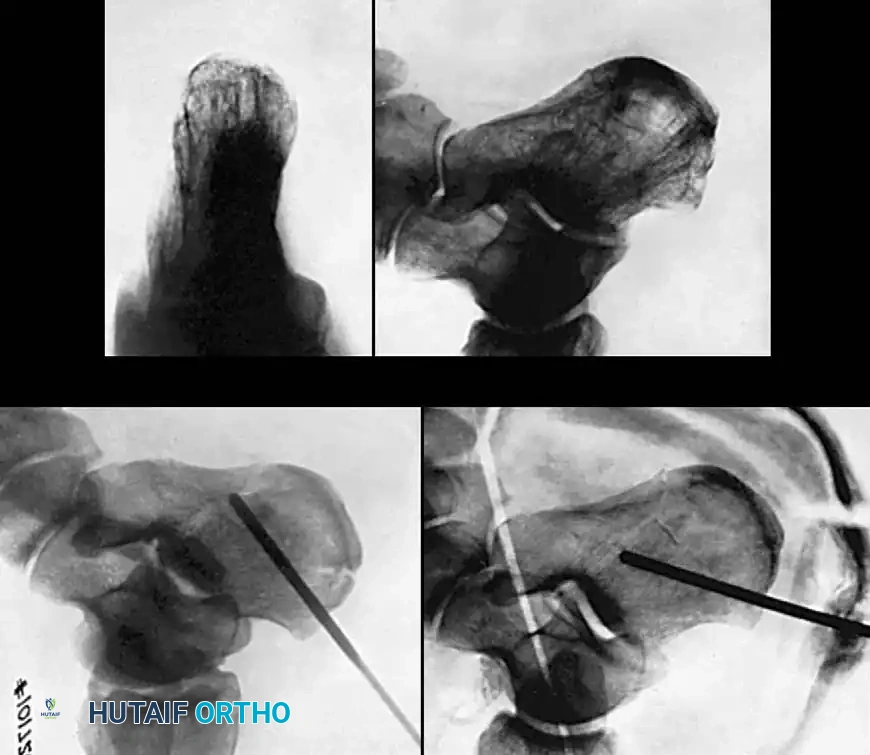

Percutaneous and Minimally Invasive Techniques

For specific fracture patterns, particularly the Essex-Lopresti Tongue-Type fractures, percutaneous reduction and screw fixation can yield excellent results with minimal soft-tissue risk.

Using the classic Essex-Lopresti maneuver, a heavy Schanz pin or Steinmann pin is introduced percutaneously into the posterior aspect of the tongue fragment. The knee is flexed to relax the Achilles tendon, and the pin is used to lever the fragment plantarly, restoring the posterior facet congruity.

Once reduced, the fragment is secured with percutaneous cannulated screws directed from the posterior tuberosity into the anterior calcaneus.